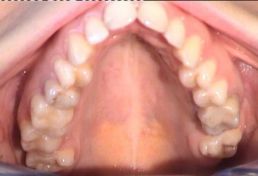

Trattamento ortodontico di una grave II Classe, paziente di sesso femminile di Età 23 anni

Trattamento ortodontico di una grave II Classe, paziente di sesso femminile di Età 23 anni.

Durata del trattamento circa due anni.

Foto iniziali